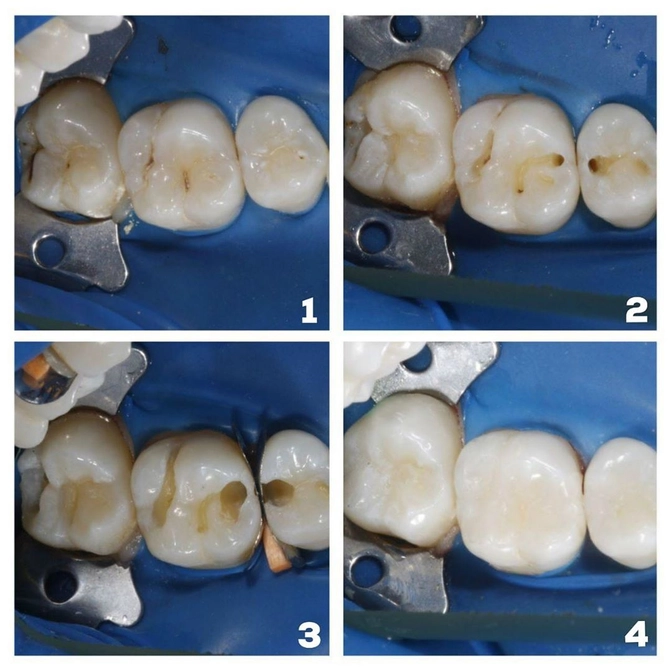

Приглядитесь, вроде бы ничего криминального, обычный поверхностный кариес в фиссуре, нооо...

Оказалось, кариес "проел" там глубоооокие полости!

Пришел пациент с жалобой, что зубы реагируют на холодную пищу.

С виду на зубах просто черные полосочки, но под ними выявлены скрытые кариозные полости, причем достаточно глубокие.

Поэтому и была чувствительность на холод.

На фото наглядно видны этапы До/Во время обработки/После.

Видите, насколько глубоко ушел обычный кариес?

При этом в процессе лечения выявлен еще и кариес на контактной поверхности зуба с соседом.

Доктор Шокуров все почистил, кариес убрал.

Восстановил "пятерку", и "шестерку", и «семерку»